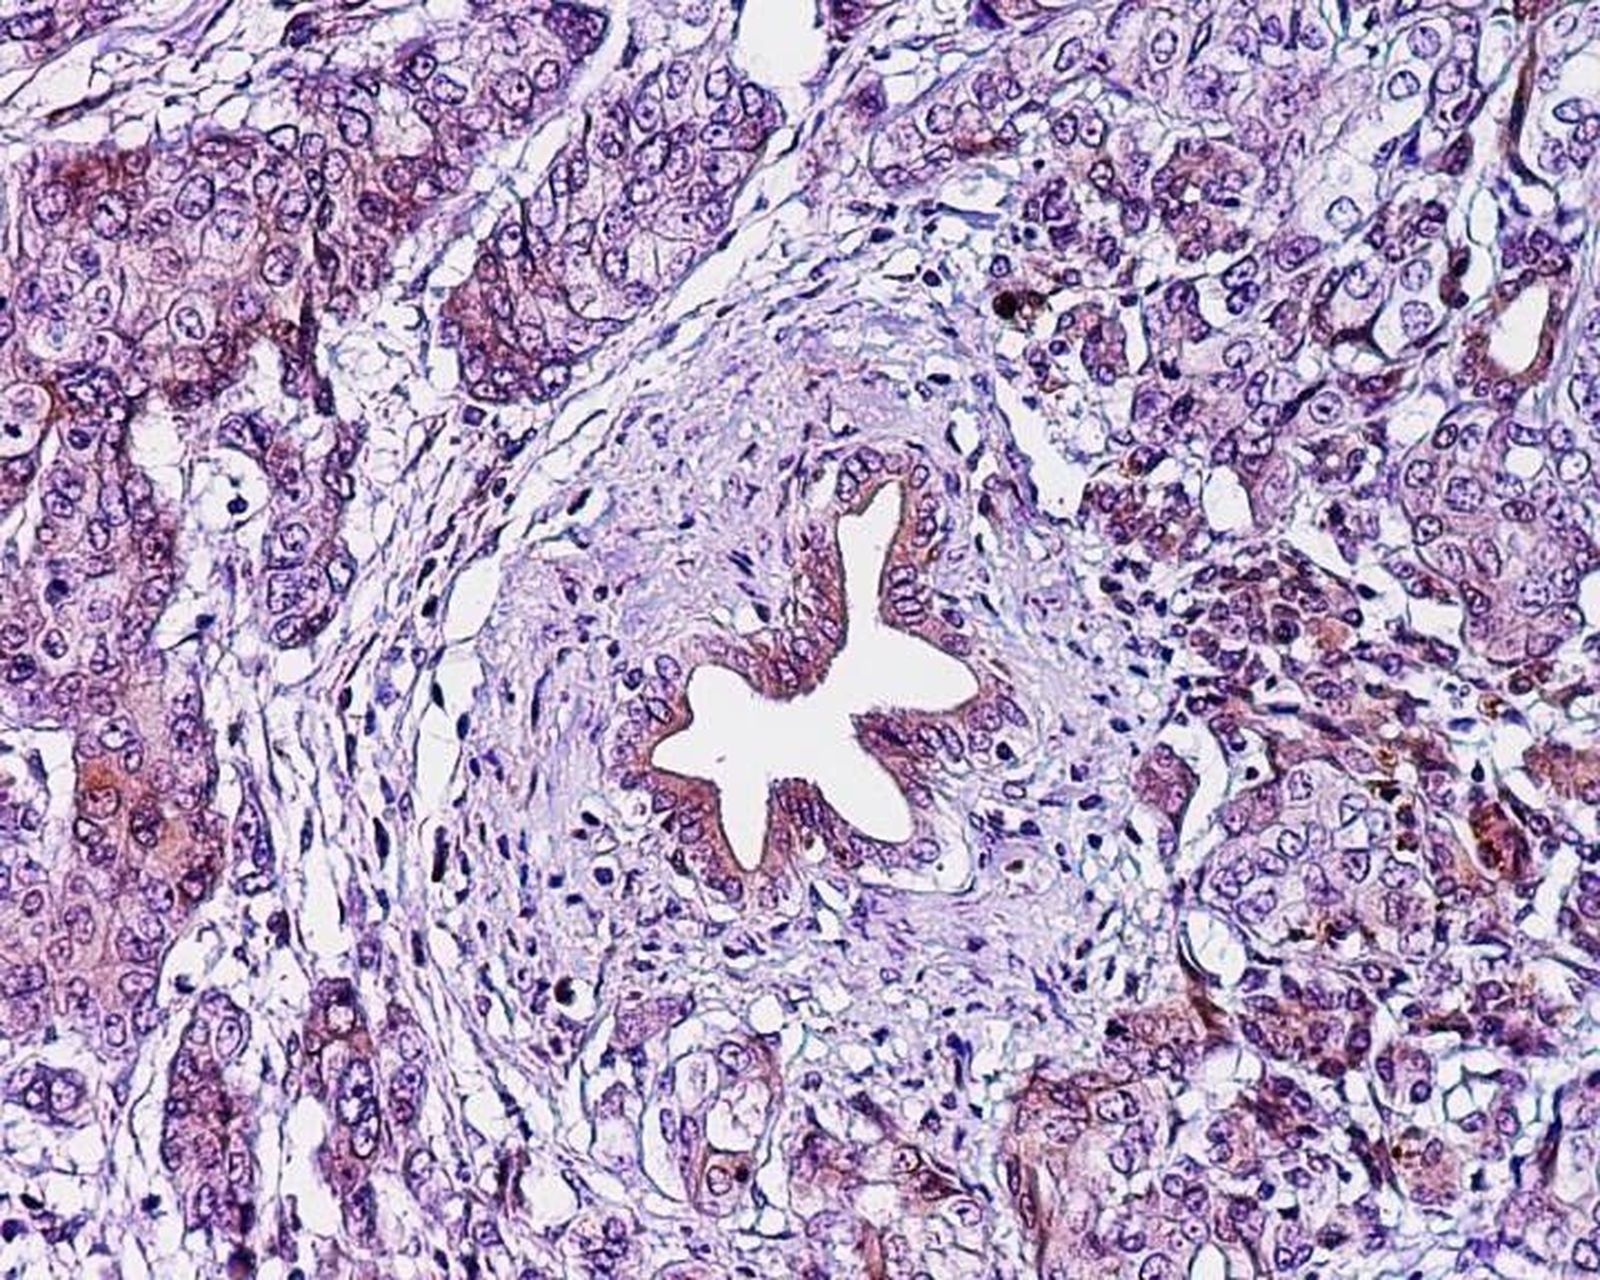

Investigadores de la Universidad de Tel Aviv en Israel están trabajando en una nueva molécula capaz de "erradicar eficientemente" las células de cáncer de páncreas desencadenando su autodestrucción, según han observado en un estudio realizado con xenoinjertos, es decir trasplantes de cáncer de páncreas humano en ratones inmunocomprometidos.

Los ratones fueron tratados con una molécula llamada PJ34, que es permeable en la membrana celular pero afecta exclusivamente a las células cancerosas humanas. Esta molécula causa una anomalía durante la duplicación de las células cancerosas humanas, provocando su rápida muerte celular. Por lo tanto, la multiplicación celular en sí resultó en la muerte celular en las células cancerosas tratadas.

Un mes después de ser inyectados con PJ34 diariamente durante 14 días, las células de cáncer de páncreas en los tumores de los ratones tratados experimentaron una caída relativa del 90 por ciento. Incluso, en uno de los ratones con el xenoinjerto el tumor desapareció por completo.